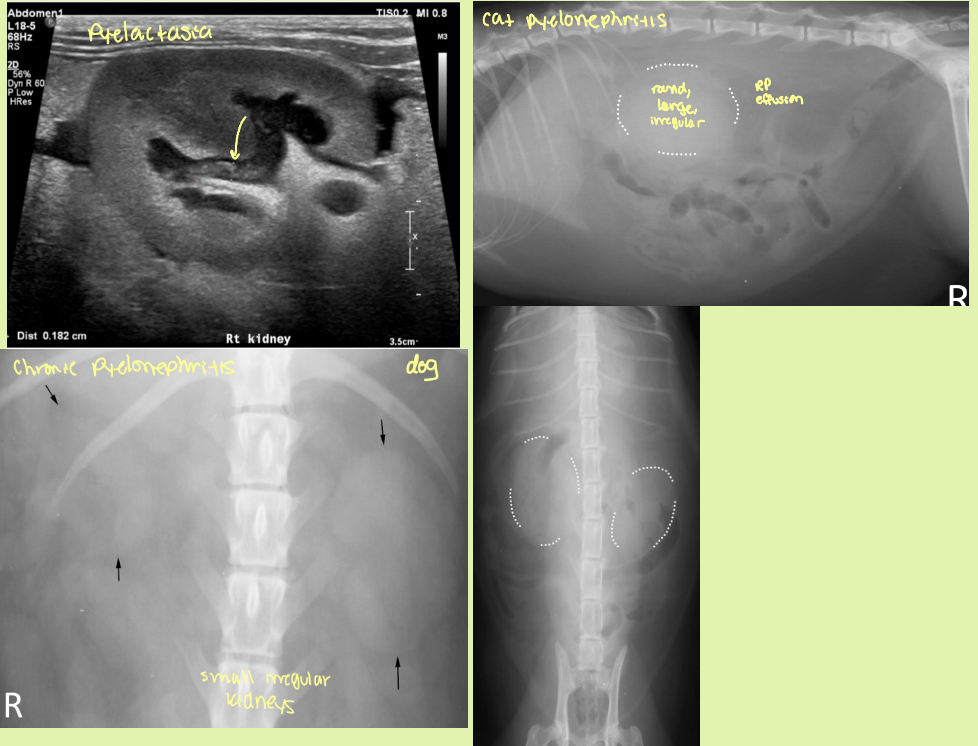

when in the disease process can you see pyelonephritis on rads

chronic or healed

2 causes of pyelonephritis

hematogenous or ascending infxn

acute vs chronic pyelonephritis rad and ultrasound findings

acute

slight enlargement of kidneys ± RP effusion

smooth contours and diffusely hyperechoic

↓CM distinction

pus/echogenic content in pelvis

pyelectasia

Chronic

small to normal sized kidneys with irregular shape

pelvis distorted

small, irregularly lumpy, bumpy shaped kidneys, ↓CM distinction ± mineralization

end stage kidneys